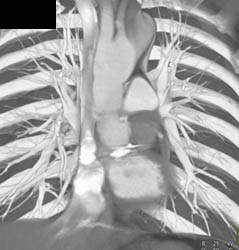

Diseased Leaflet Aortic Valve